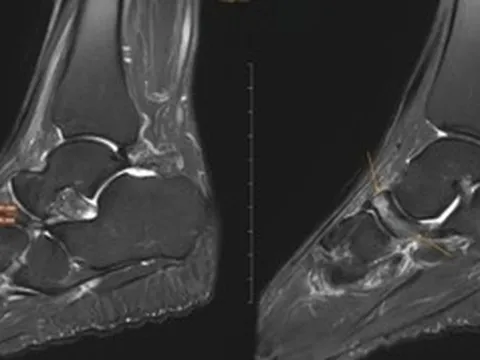

Ngay sau đó, các bác sĩ đã nhanh chóng tiến hành chụp cắt lớp vi tính bụng, tiểu khung, lồng ngực, sọ não và thực hiện các xét nghiệm cận lâm sàng, hội chẩn các chuyên khoa Cấp cứu, Hồi sức tích cực – chống độc, Khoa Ngoại nhi.

Kết quả chẩn đoán cho thấy, trẻ bị suy hô hấp độ 3, sốc chấn thương, đa chấn thương. Bé gái còn bị chấn thương ngực kín, gãy xương sườn bên trái, đụng dập nhu mô, tràn khí – tràn máu màng phổi hai bên, chấn thương bụng kín, chấn thương gan độ 3, chấn thương lách độ 3.